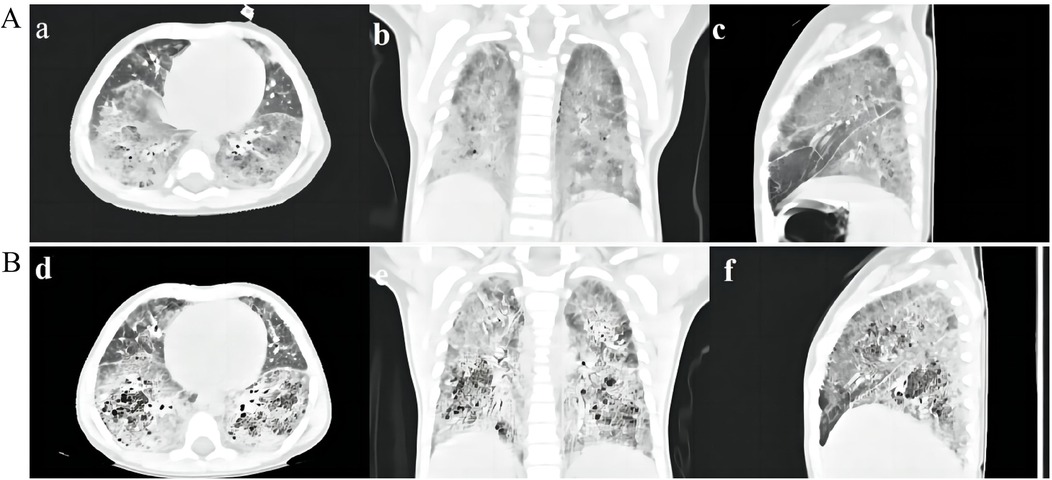

After being admitted to our hospital, her serum thyroid hormones level indicated a significant increase in thyroid-stimulating hormone TSH (63.903 μIU/mL, normal range, NR 0.36–7.63) and low thyroxine levels (10.48 pmol/L, NR 13.17–22.33). Complete blood counts, serum electrolyte levels, liver and kidney function, and myocardial enzyme levels were within the normal ranges. No immune function abnormalities were found. The results of nasopharyngeal swab tests, bronchoalveolar lavage for a respiratory viral panel by polymerase chain reaction (PCR), and blood culture were all negative. Fiberoptic bronchoscopy and alveolar lavage were performed and the bronchoalveolar lavage fluid (BALF) was limpid. Chest radiography revealed multifocal opacities in both lung fields, and chest high-resolution computed tomography (HRCT) revealed diffuse reticular and bilateral patchy ground-glass opacities (Figures 1A-a–c). Owing to hypotonia and neurodevelopmental delay, a brain MRI was performed, the results of which were normal. Echocardiography revealed resolved pulmonary hypertension. Sanger sequencing was performed on the patient and her parents, which identified a heterozygous de novo missense pathogenic variant in the NKX2-1 gene [NM_001079668.3:c.583C>T (p.Arg195Trp)], c.583C>T in exon 3 in the patient; neither of her parents had the pathogenic variant (Figure 2). This missense variant resulted in the substitution of an arginine (Arg) residue with tryptophan (Trp) at codon 195 (p.Arg195Trp). It did not change the secondary structure of the protein but resulted in the disappearance of two hydrogen bonds between amino acids 195 and 401, thus resulting in a dysfunction of the DNA-binding domain (DBD) (Figure 3).

Figure 1. (A) HRCT scan of the patient. HRCT scan at 7 months of age showing diffuse reticular and bilateral asymmetrical ground-glass opacities (a–c). (B) HRCT scan 2 months after discharge showing multiple cysts and crazy-paving stone signs in both lung fields (d–f).

According to the clinical phenotypes and genetic analysis, the patient was confirmed to have brain–lung–thyroid syndrome stemming from a pathogenic variant of the NKX2-1 gene. Apart from continued administration of thyroid hormone replacement therapy, the infant was treated with nutritional supplementation and high-flow nasal cannula (HFNC) oxygen therapy, in which the parameters showed that the fraction of inspired oxygen (FiO2) was 36% and the oxygen flow rate was 20 L/min (the weight of the patient was 6.2 kg). She was suggested to receive glucocorticoid treatment, but in consideration of her young age, poor nutritional status, and adverse reactions to glucocorticoids, her parents refused the therapeutic regimen. Subsequently, she received trial treatment with hydroxychloroquine (HCQ) 10 mg/kg/day. She still required HFNC (FiO2, 32%; oxygen flow rate, 12 L/min) and nasogastric feeding upon discharge from the hospital. Following discharge after 2 months, she was off HFNC and required a nasal oxygen supplementation (low-flow oxygen therapy, FiO225%–28% at 0.5–1 L/min), HRCT showed a worsening status that demonstrated a crazy-paving stone sign and multiple cysts (Figures 1B-e,f). HCQ was discontinued following liver insufficiency, and she is still under follow-up.

NKX2-1 gene pathogenic variant–associated clinical phenotypes are highly multitudinous (16); only approximately half of the patients manifest the full triad of brain–lung–thyroid syndrome, approximately a quarter of them show an isolated respiratory phenotype, and one-fifth of them have neurological symptoms associated with the respiratory phenotype (17, 18). In our study, we found that the patient demonstrated typical triad manifestations similar to those found in several previous reports. Our patient had RDS during her neonatal period; at the same time, congenital hypothyroidism was identified. The infant gradually developed neurological symptoms, including hypotonia and feeding difficulties, and subsequently developed ILD. Her imaging features showed representative ground-glass opacities, as previously reported (19), and subsequent HRCT demonstrated the evolution of crazy-paving stone signs and multiple cysts over time. Thus far, no specific therapeutic strategy has been developed for children with NKX2-1 pathogenic variants (1). General measures are essential, including exogenous surfactant therapy for patients presenting with acute respiratory distress in the neonatal period, oxygen supplementation for chronic hypoxemia, thyroid hormone replacement therapy, and maintenance of nutrition. In addition to general measures, pharmacological therapies such as corticosteroids, HCQ, and azithromycin may play anti-inflammatory and immunosuppressive roles and have been reported to be effective in some cases with NKX2-1 pathogenic variants (20). Lung transplantation may be the ultimate therapy for prolonging survival in children with end-stage progressive disease (21).